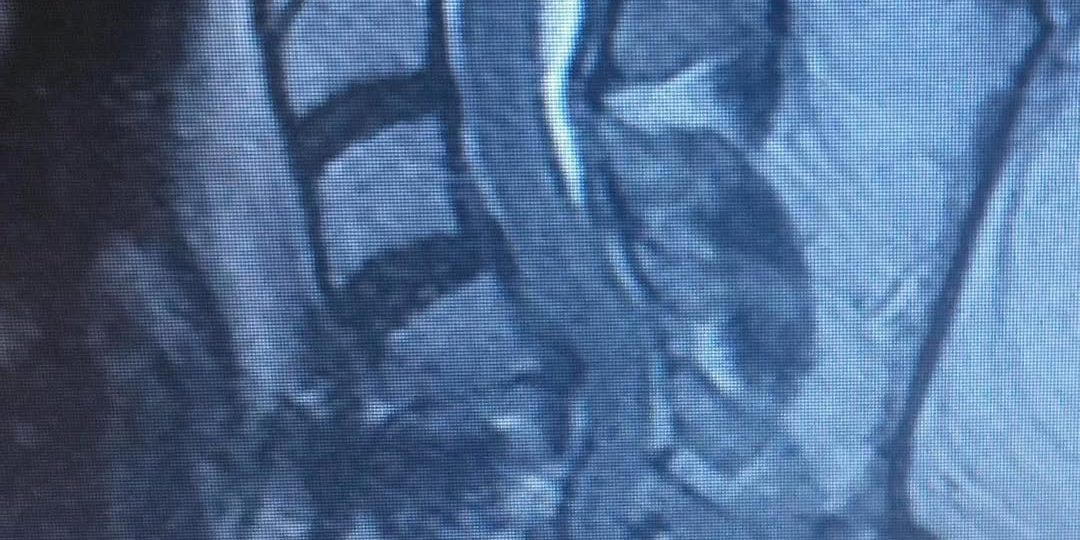

Kyphosis is the opposite of lordosis. Cervical means relating to the neck. While the human anatomy has curves, cervical kyphosis is either an abnormally straight neck spine or one that’s bent backward. The straighter or more pronounced the neck spine is, the more serious the condition tends to be with more side effects.

Here is an extreme example of a patient who came to me for correction of a previous attempt at surgery which failed to correct her severe Kyphosis and spinal cord compression. After the much more extensive surgery that I performed, she began to recover strength in her arms again and her ability to walk improved.